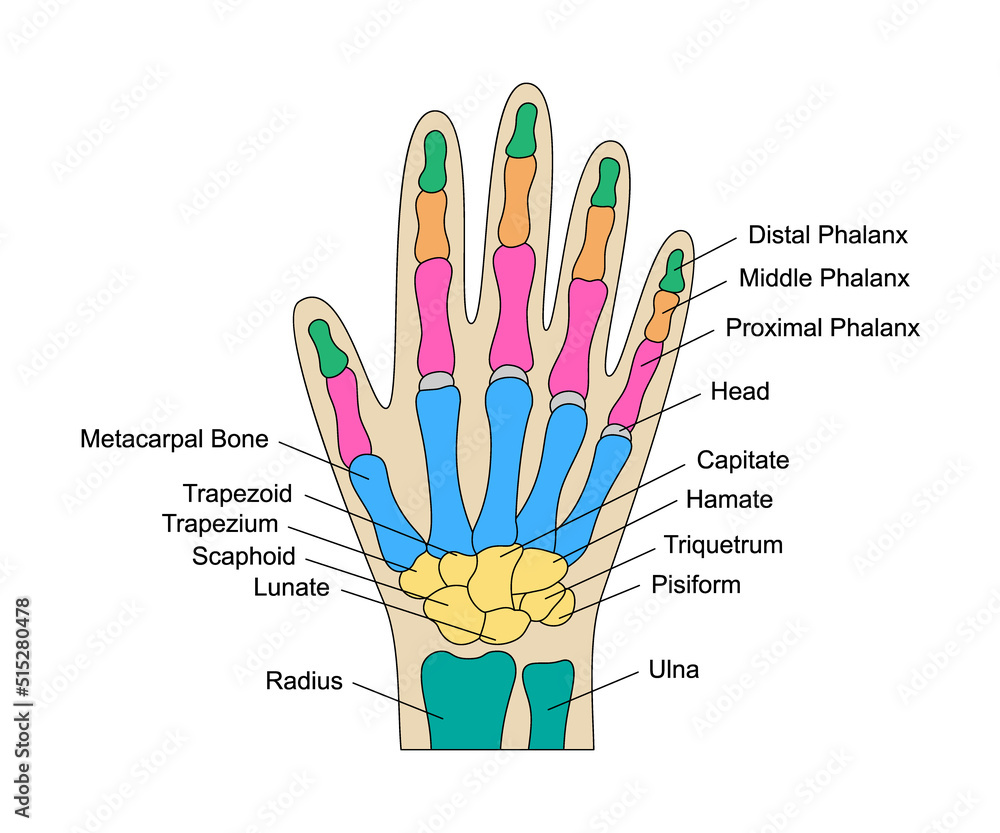

Las manos están formadas por más huesos y partes móviles que cualquier otra zona del cuerpo. Si están sanas, estas partes funcionan en conjunto. Realizan una gran cantidad de tareas. Las manos pueden hacer movimientos muy delicados. También pueden hacer tareas que requieren de mucha fuerza. Huesos.. Están localizadas en los extremos de los antebrazos, son prensiles y tienen cinco dedos cada una. A continuación os presentamos las 15 partes de la mano y sus funciones. 1. Los huesos de la mano. La mano humana está compuesta por un total de 27 huesos diferenciados en tres zonas en función de su posición.

Cada dedo tiene tres falanges (distal, media y proximal); solamente el pulgar tiene dos. Huesos metacarpianos. Los cinco huesos que componen la parte media de la mano. Huesos carpianos. Los ocho huesos que forman la muñeca. Los huesos carpianos están conectados a dos huesos del brazo–el hueso cúbito y el hueso radio.. falange: Uno de los huesos de los dígitos. Carpas de la mano izquierda: Hay ocho huesos carpianos en cada muñeca: escafoides, lunados, triquetrales, pisiformes, trapecios, trapecios, capitados y hamates. La mano contiene 27 huesos. Cada una pertenece a una de tres regiones: los carpos, (muñeca), los metacarpianos, (la palma) y las falanges.